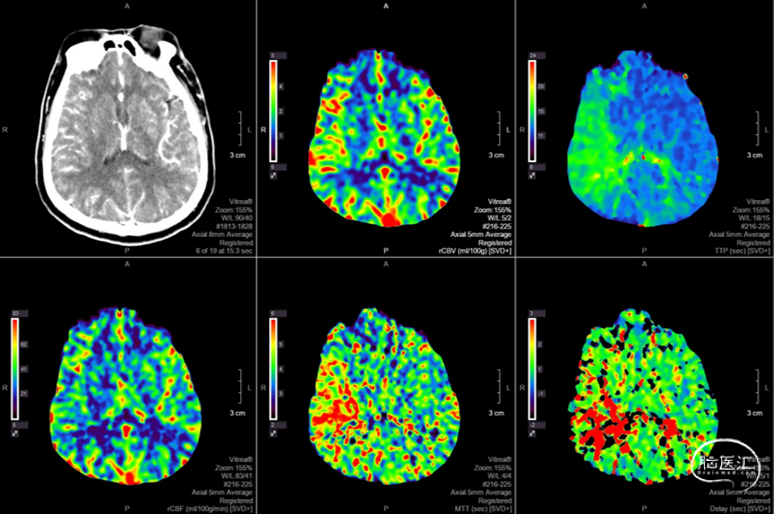

头颅CTP:右侧大脑中动脉区域明显低灌。